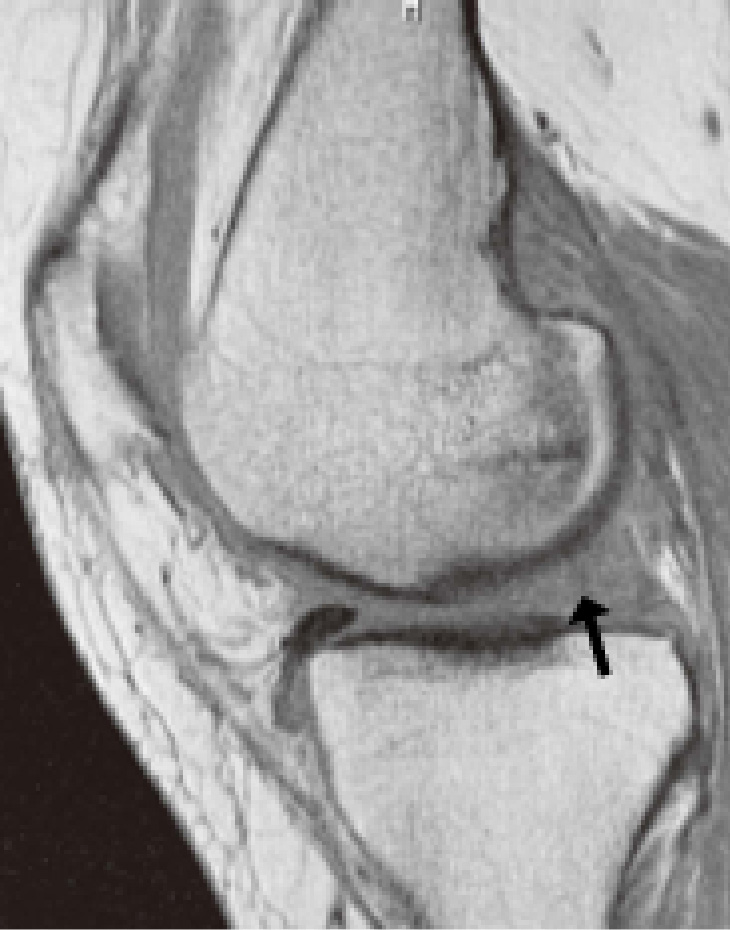

MRIで確認されるBMLや内側半月板後根断裂(MMPRT)は進行の引き金となるため早期受診が重要です。

- MRI検査

- レントゲンでは分からない

・軟骨の損傷

・半月板の断裂

・骨の中のむくみ(BML:骨髄病変) などを詳しく確認します。